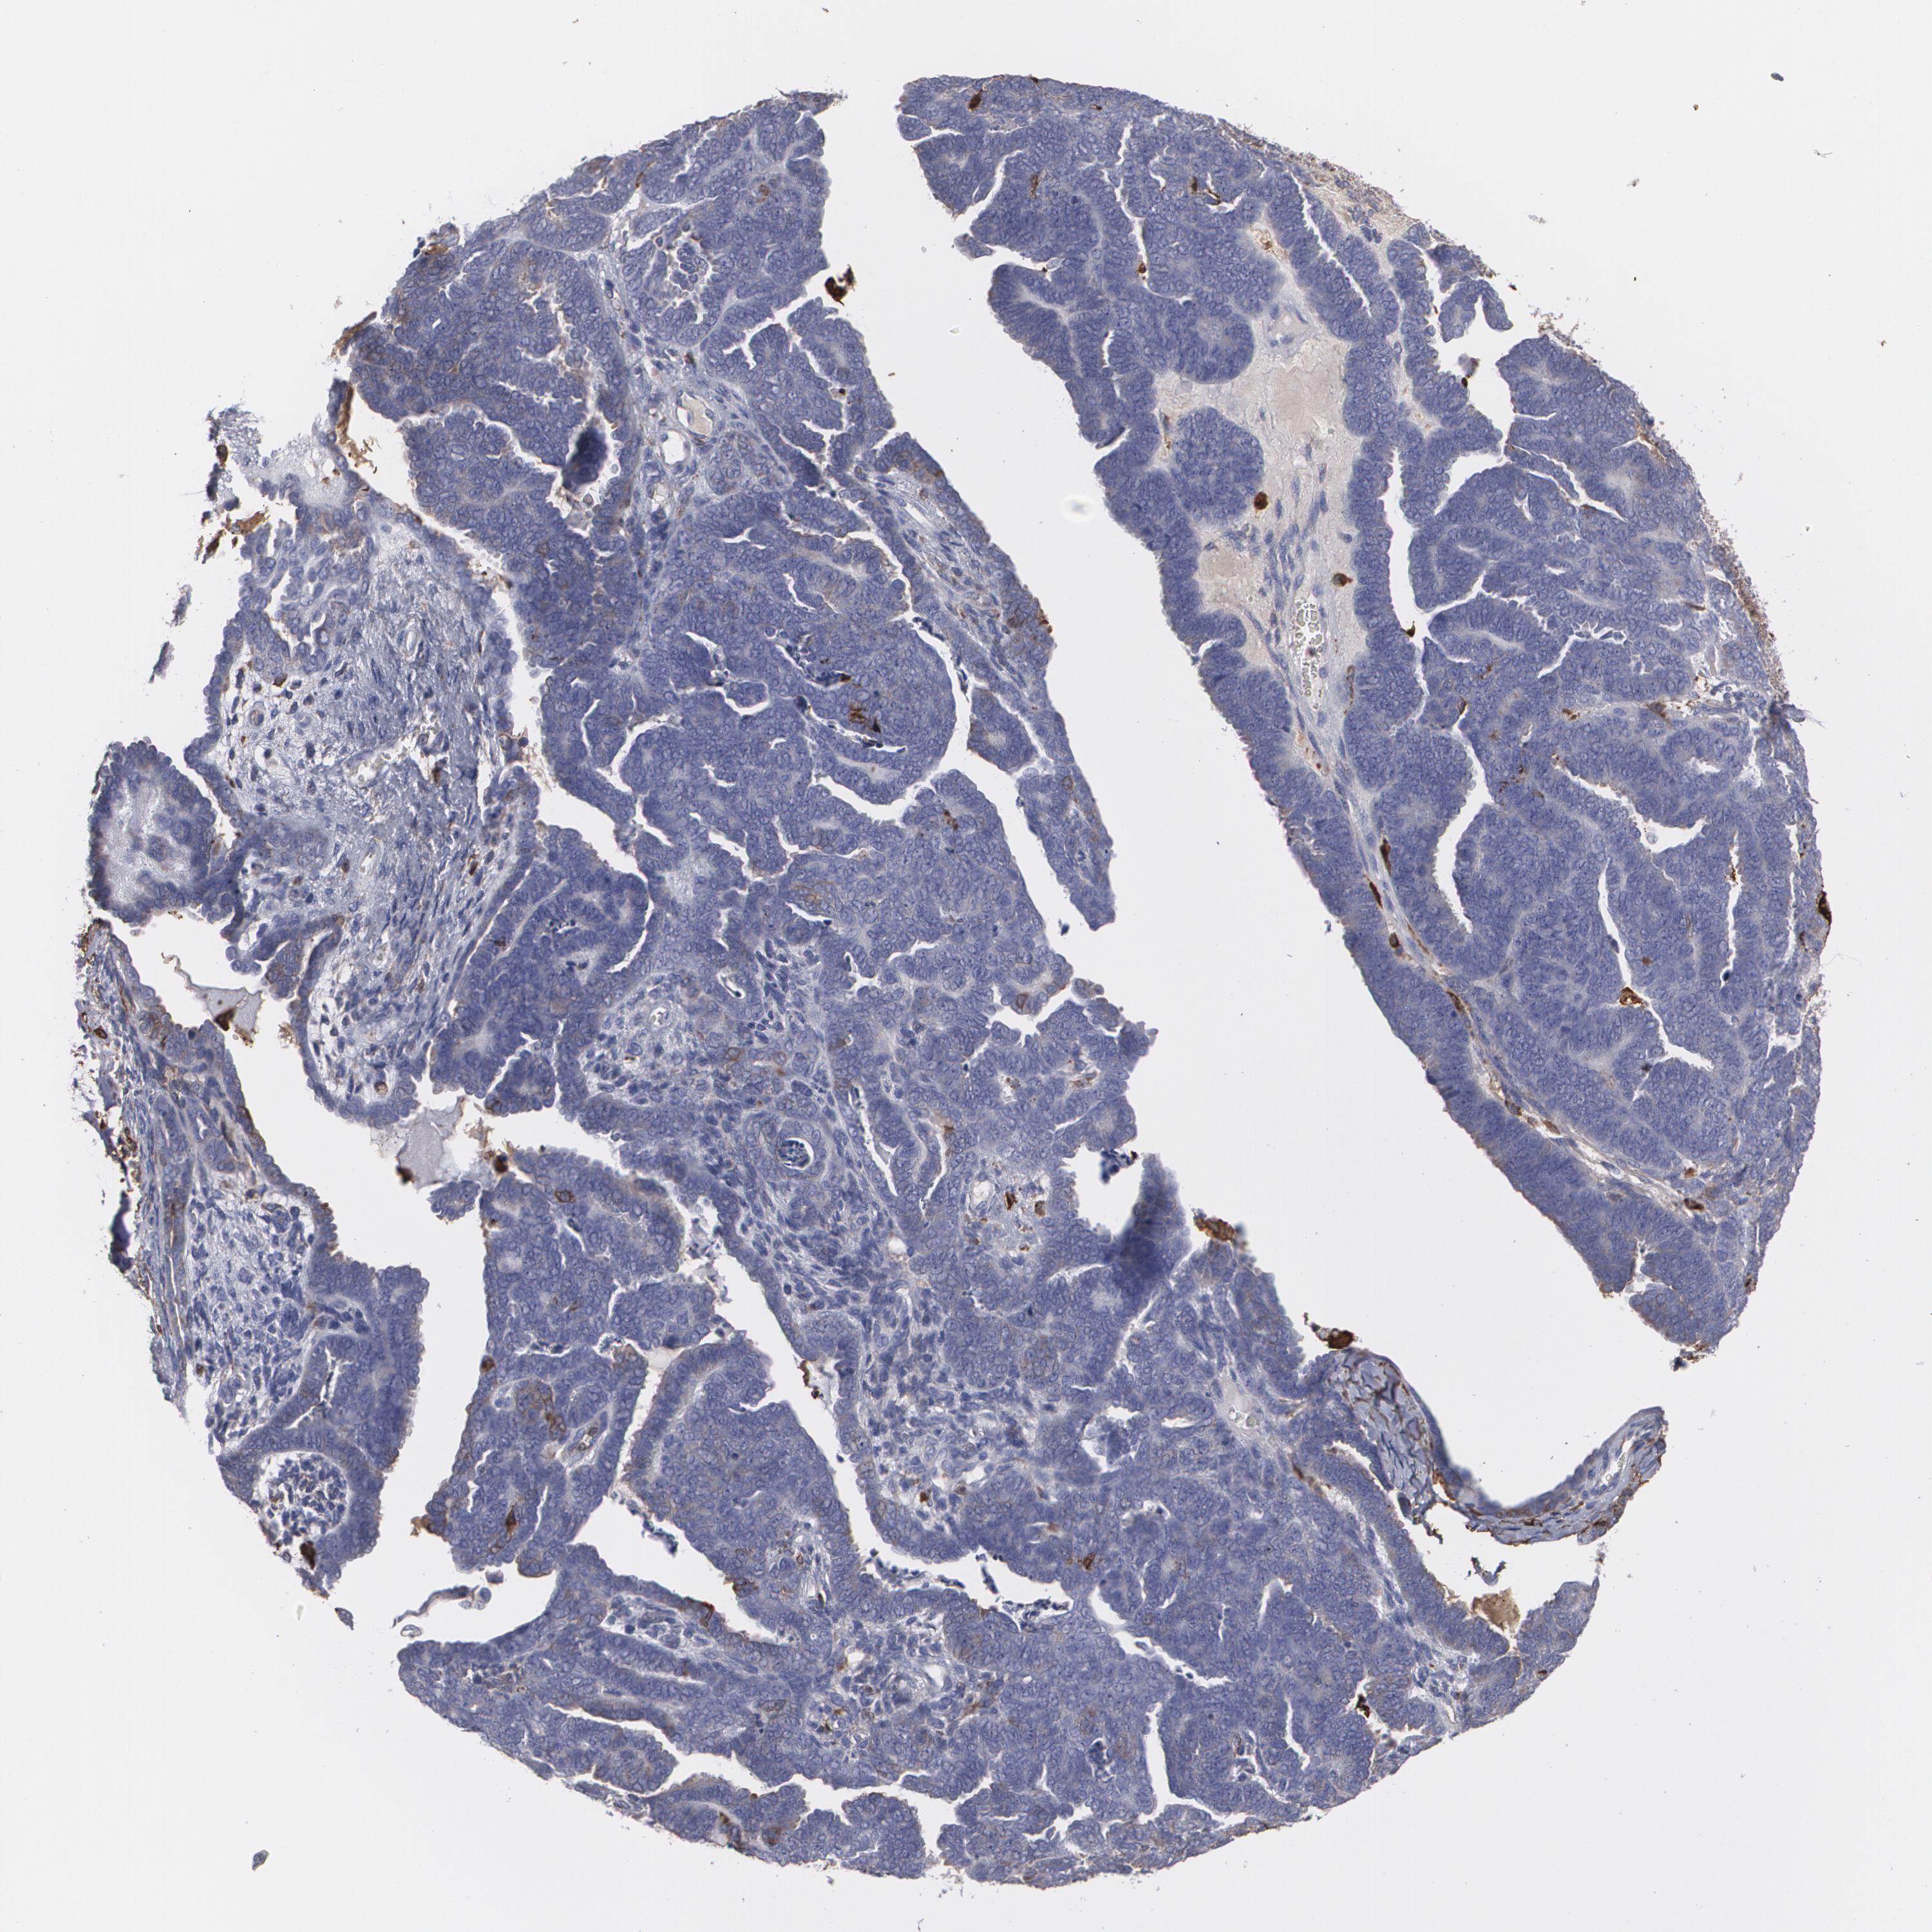

ENDOMETRIAL CANCER - Protein expressioni

A mouse-over function shows sample information and annotation data. Click on an image to view it in a full screen mode. Samples can be filtered based on level of antibody staining by selecting one or several of the following categories: high, medium, low and not detected. The assay and annotation is described here.

Note that samples used for immunohistochemistry by the Human Protein Atlas do not correspond to samples in the TCGA dataset.

Antibody stainingi

Antibody staining in the annotated cell types in the current human tissue is reported as not detected, low, medium, or high, based on conventional immunohistochemistry profiling in selected tissues. This score is based on the combination of the staining intensity and fraction of stained cells.

Each image is clickable and will lead to virtual microscopy that enables deeper exploration of all samples and also displays staining intensity scores, fraction scores and subcellular localization as well as patient and tissue information for each sample.

Antibody HPA001536

Antibody CAB035996

Staining

High

Medium

Low

Not detected

Intensity

Strong

Moderate

Weak

Negative

Quantity

>75%

75%-25%

<25%

None

Location

Nuclear

Cytoplasmic/membranous

Cytoplasmic/membranous,nuclear

Adenocarcinoma, NOS

Neoplasm, malignant, NOS

Adenocarcinoma, metastatic, NOS